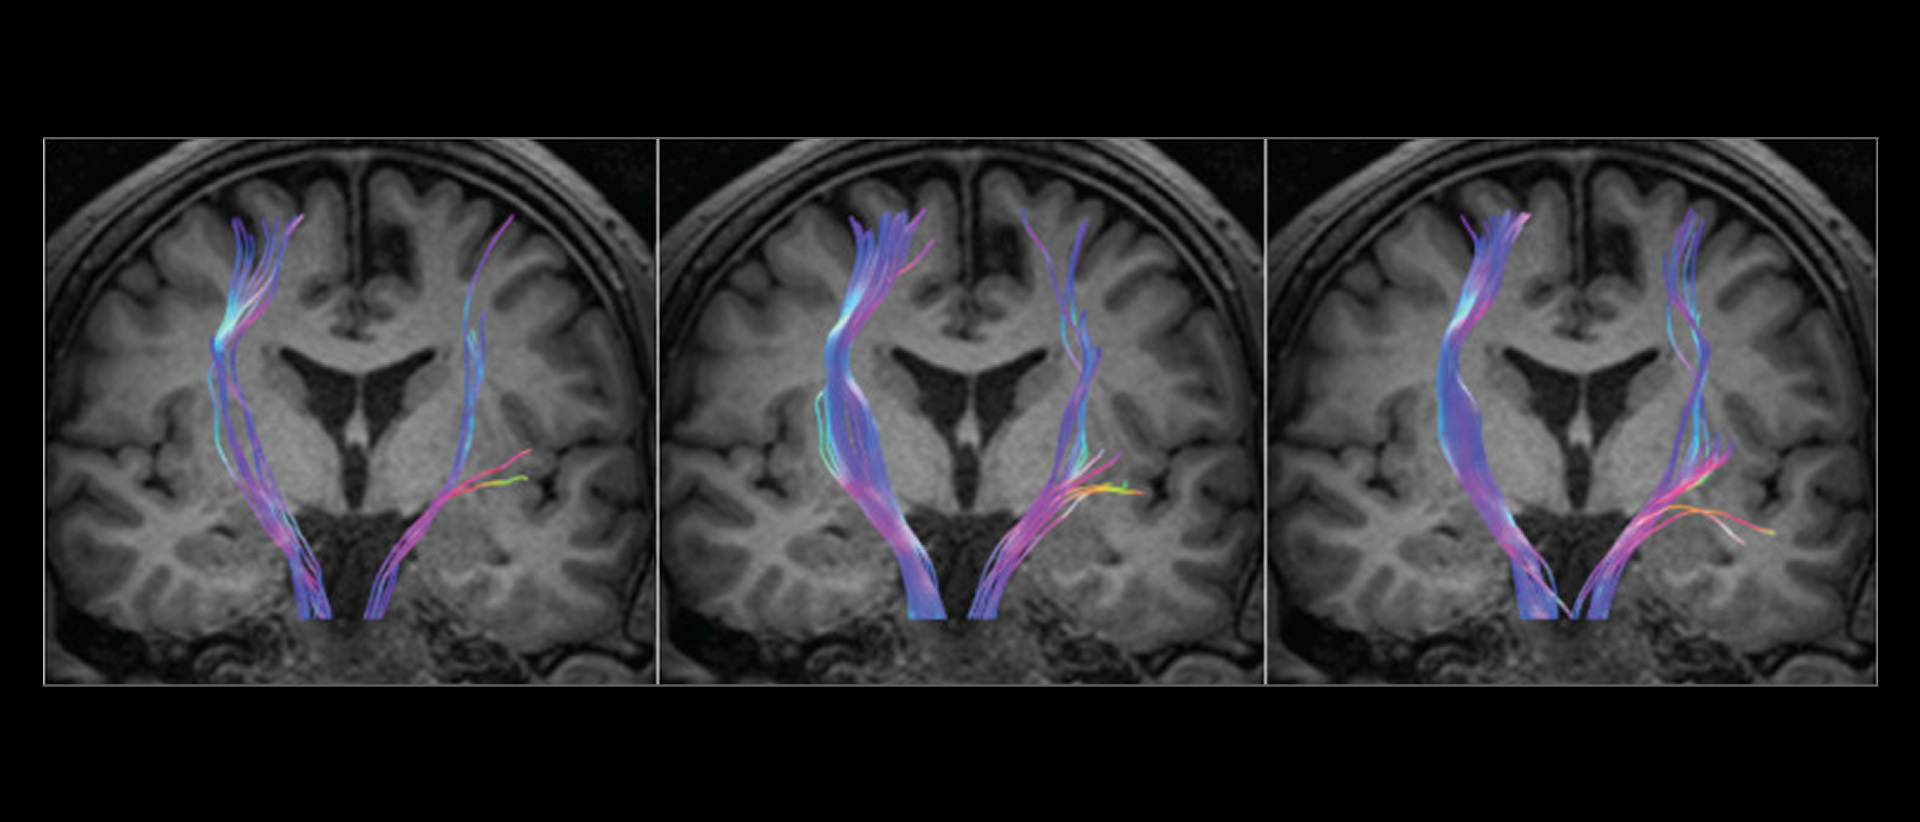

Artículos orientados a Médicos Radiólogos con casos reales de nuestras clínicas